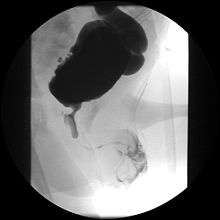

Voiding cystourethrogram (VCUG) is more specific for the diagnosis. Normal plicae circularis are variable in appearance and often not seen on normal VCUGs. PUV on voiding cystourethrogram is characterized by an abrupt tapering of urethral caliber near the verumontanum, with the specific level depending on the developmental variant. Vesicoureteral reflux is also seen in over 50% of cases.